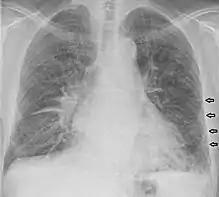

Lignes de Kerley B chez un patient souffrant d'insuffisance cardiaque congestive.

Les lignes de Kerley sont un signe de syndrome interstitiel sur une radiographie du thorax. Elles traduisent l'épaississement des septa interlobulaires dû à un infiltrat du tissu conjonctif (interstitium pulmonaire). On distingue les lignes de Kerley de type A (apical), B (basal), C (apical+basal) et D[1].